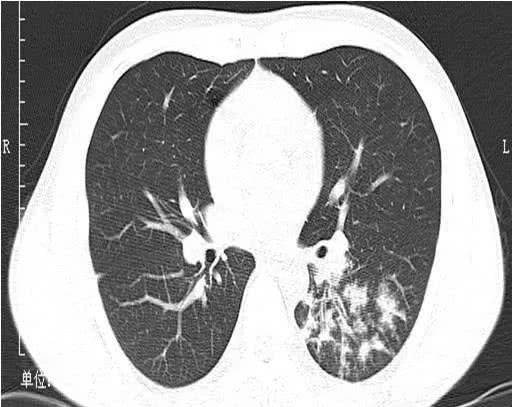

女孩脸上额头长了疖子,想着把疖子挤出来会更好。结果用力挤压后,引起眼眶感染,细菌进入血液循环并在血液中繁殖,引起败血症。除了发烧,这些有毒的金黄色葡萄球菌还被种植在肺部,造成十几个空洞。